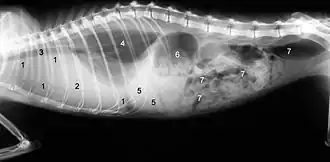

1 cień rozlany spowodowany płynem w dolnej części klatki piersiowej, 2 serce bez widocznych konturów z powodu płynu, 3 tchawica, 4 płuco (tylko niewielka część jest wciąż wentylowana), 5 wątroba, 6 żołądek, 7 jelita